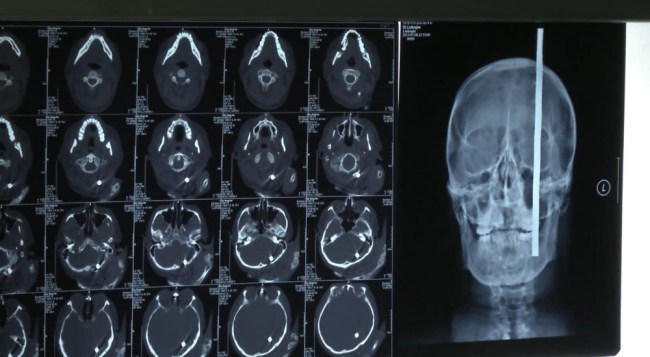

Строител по чудо оцеля с 46 см прът, набучен в главата! (ФОТО)

Поредният случай, при който човек оцеля с пронизан открай докрай мозък, изуми дори опитни лекари Мозъкът на човека остава една от най-големите загадки за науката. Случаят с китайски строител, който оцеля след като 46 сантиметров железен прът бе пронизал главата му, е същинско чудо. Както посочва британският сайт metro.co.uk, позовавайки се на агенция China News, строителят е участвал в изграждането …